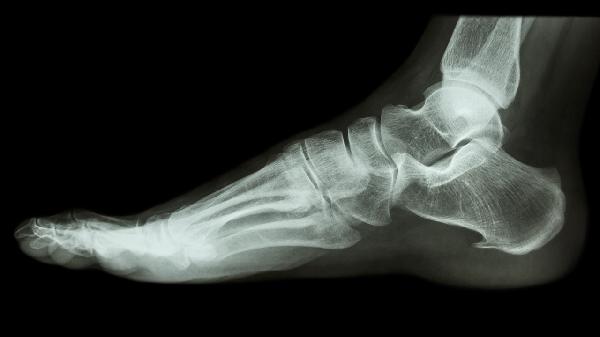

骨裂后需立即通过石膏、支具或外固定架限制患肢活动,避免骨折端移位。上肢骨裂常用前臂石膏,下肢骨裂需配合拐杖减少负重。固定时间通常为4-8周,期间需定期复查X线观察愈合情况。若固定不当可能导致畸形愈合或延迟愈合。